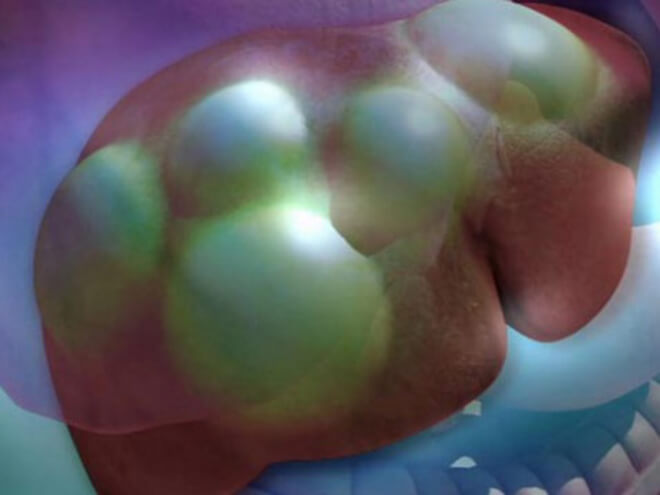

После заглатывания яиц эхинококка, они попадают в кишечник. Здесь из яиц уже выходят личинки, которые активно «пробуривают» стенку кишечника и проникают в кровеносные сосуды. С током крови эхинококк заносится во внутренние органы, где образует кисты с жидкостью, которые могут достигать двадцати сантиметров в диаметре. В кистах находится множество сколексов (головок паразита).

Первый барьер на пути продвижения эхинококка — печень. В большинстве случаев эхинококк «застревает» в печени, формируя в ее тканях кисты. Если же гельминту удается пройти этот барьер, он попадает в легкие. В редчайших случаях «путешествие» эхинококка продолжается, и тогда из легких он кровью заносится в мозг, почки, сердце, кости.

При альвеолярном эхинококкозе формируется многокамерная киста. По сути это конгломерат мелких пузырьков. Величина кисты может быть от одного до тридцати сантиметров в диаметре. Чаще всего при альвеококкозе поражается печень.